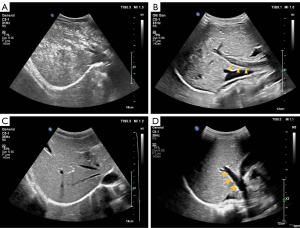

After intravenously administered contrast-enhanced agent, the hyperechoic hepatic enhancement pattern was observed along portal branches. Using the conventional B-mode and switching to the CEUS mode did not influence the appearance of hyperechoic spots. The PHLE phenomenon began to appear within 30 minutes to 1.5 hours after the intravenous injection of SonoVue®, and lasted for 30 minutes to 5 hours. Conventional B-mode ultrasound showed no sign of hepatic hyperechogenicity in two patients who underwent a second CEUS examination approximately 24 hours after the first examination. Abdominal symptoms were not observed the day after the occurrence of hyperechoic staining. We summarized the characteristics of hyperechoic spots in the liver as follows:

- The PHLE pattern manifested as diffusely distributed hyperechoic spots in the liver parenchyma, located along the portal vein.

- The PHLE phenomenon was mainly focused on the right lobe of the liver. The contrast effect in the left lobe was slightly weaker than in the right lobe.

- Flowing hyperechoic spots were detected in the portal vein.

- For all the participants, hyperechoic staining was visible on both conventional B-mode and contrast-enhanced mode.

- The PHLE appearance persisted stably even at high MI under CEUS mode (1.1 to 1.3).

When the patient presented with abdominal symptoms, abdominal scanning revealed hyperechoic spots in the liver. Among 11 patients who manifested diffuse hyper-echoic staining in ultrasound, five patients experienced serious abdominal symptoms, such as abdominal pain, nausea, and even a red rash on the skin. The other six patients only showed mild abdominal discomfort, like defecation sensation or bowel movement (Figure 2). Only two patients exhibited tiny hyper-echoic spots in ultrasound. Regarding abdominal symptoms, the two patients merely presented with defecate reactions (Figure 3).

Our study found that 13 of 20 (65%) patients manifested hepatic hyperechoic spots after CEUS and were accompanied by abdominal symptoms. Meanwhile, we found that patients with PHLE manifestation had a higher proportion of containing a history of gastrointestinal disease. In this context, we speculated that it might be related to mild gastrointestinal allergic reactions. One patient (case 1) with abdominal symptoms concurred with paleness and fatigue. Another patient (case 8) showed a red rash on the skin of the abdomen, which is one manifestation of an allergic reaction. Based on the above performances, we hypothesize that SonoVue® causes a mild allergic reaction in the gastrointestinal tract, which increases the permeability of the capillaries on the surface of the intestinal wall. Thus, the gas in the intestinal tract is translated into the liver via the portal venous system. The dynamic hyperechoic spots were detected in the portal veins of most patients with obvious abdominal discomfort in our study (Figure 3B). The same performance in portal veins has also been previously reported (16,17). As the allergic reaction subsided, patients’ gastrointestinal symptoms were spontaneously relieved, and the hepatic hyperechoic staining gradually disappeared. This hypothesis was established based on some previous perspectives of delayed hepatic enhancement. We agree with Okada et al. (8) that the gas responsible for PHLE differs from the gas constituting the contrast agent microbubbles. The global volume of microbubbles was only a few milliliters, whereas the phenomenon observed was massive and continuous. Also, in Caruso et al.’s findings (9), marked hyperechogenicity was detected in the portal vein and superior mesenteric vein, confirming that the hepatic phenomenon originated from enter portal circulation.